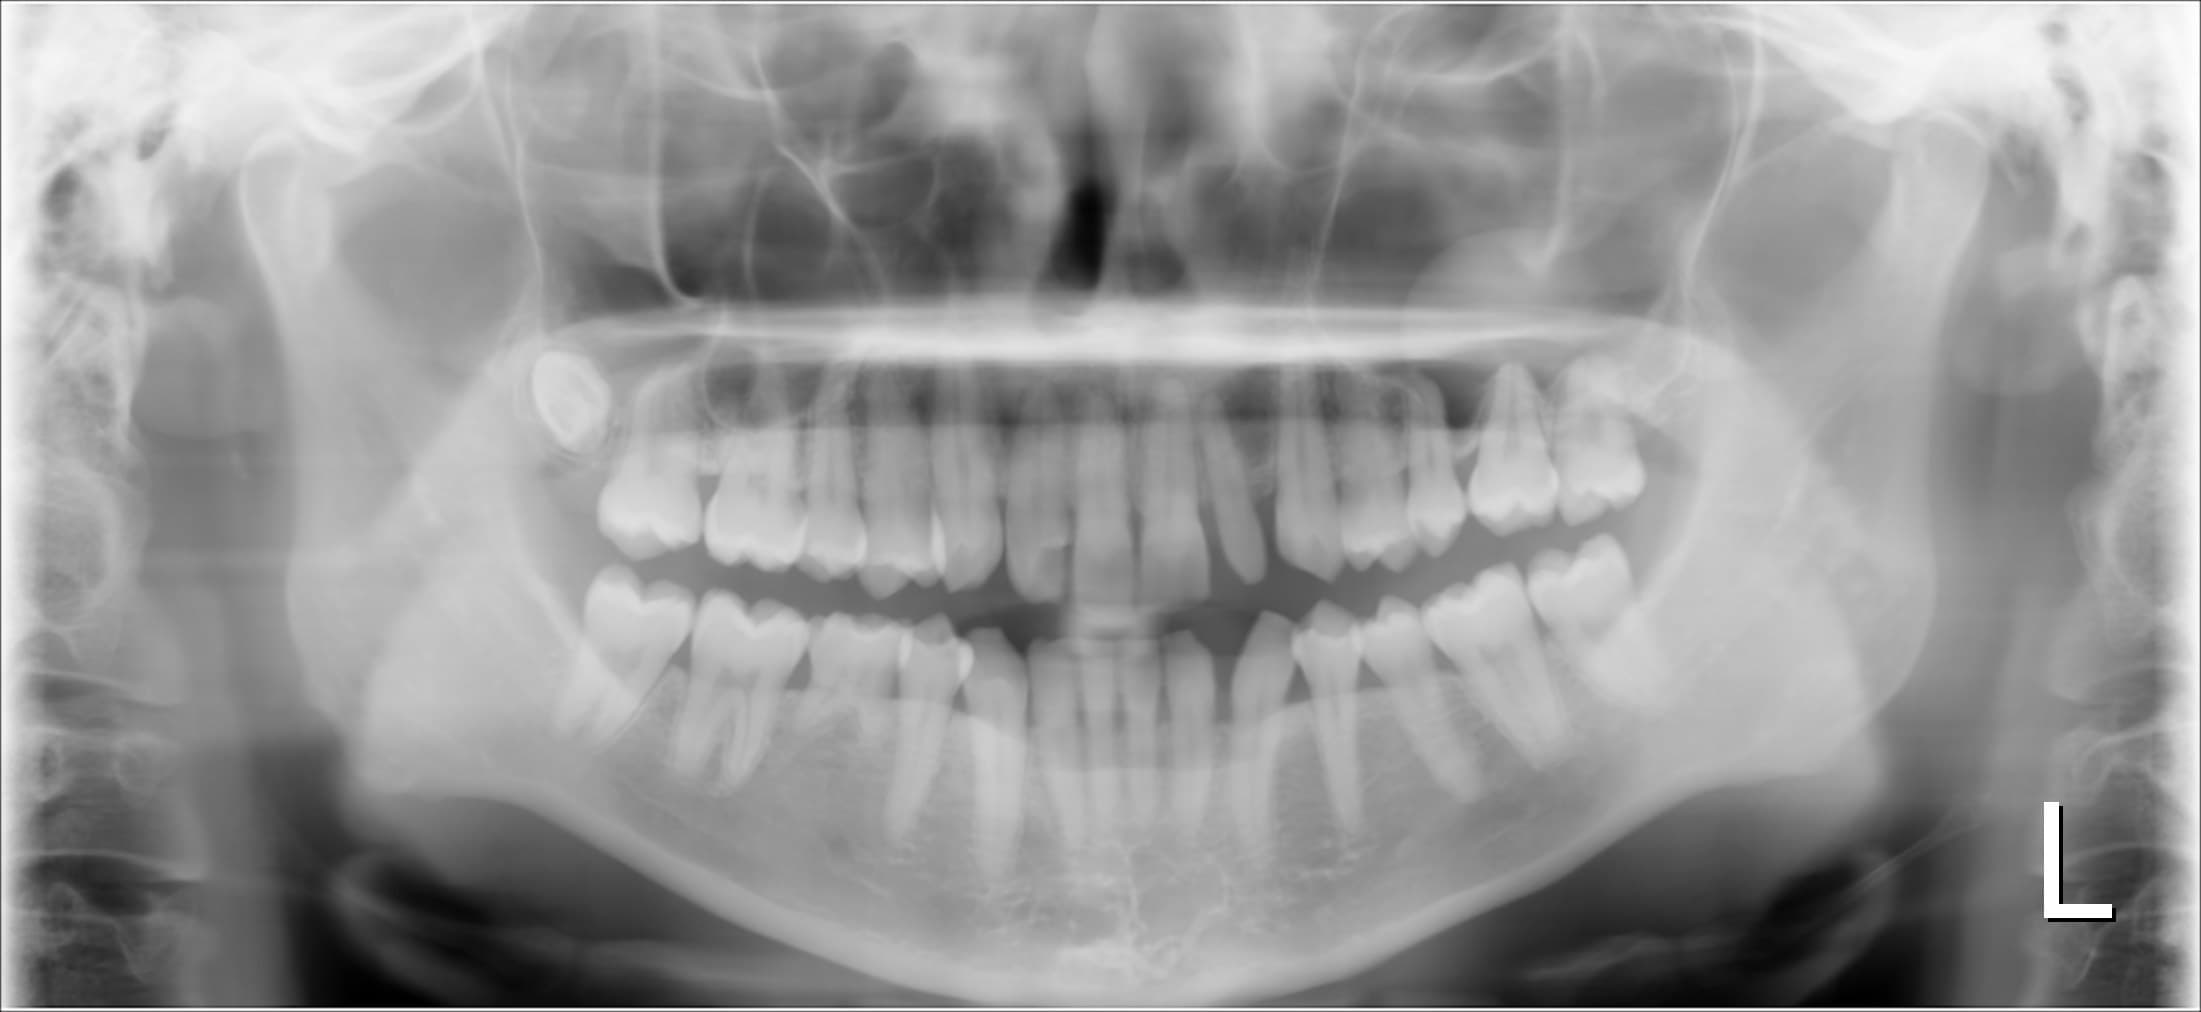

今回ご紹介する、歯周専門治療のケースは30代女性の方です。

20代の頃から、他院にて歯周病と診断され、頻繁に痛みを伴う腫れと出血を繰り返していました。

検査の結果、腫れを繰り返していたのは、歯周病が管理されていない事が原因でした。

歯周病は細菌感染が原因で起こるので、消毒や抗生物質は確かに有効なのですが、これらは歯周病の根本的な解決にはなりません。

先ず、必要なのは原因になる細菌の除去と正常な細菌叢に戻す治療です。